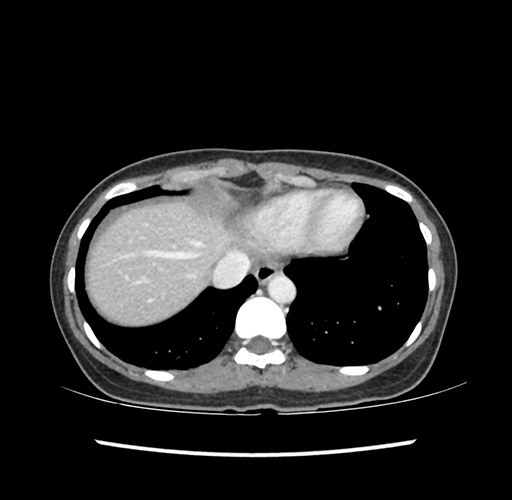

Imaging Analysis

Look through the patient's CT scan to identify any areas of concern for the necessary procedure.

Based on your CT findings, which issue(s) would give reason for "planned slowing down moment(s)" in this case?